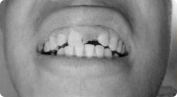

题目:患者,男,38 岁。上前牙变色 1 年,自述上前牙 5 年前受过外伤,唇侧倾斜,检查可见左上 1 牙冠变色,牙冠缺损近 1/2,牙髓测试无反应,X 线根尖片显示患牙无明显异常,全景片显示双侧下颌智齿近中阻生,之前有发炎化脓病史,目前无咀嚼不适。口腔其余无异常。检查情况及X线片见下图:

1.主诉诊断:左上 1 牙髓坏死(外伤)

非主诉诊断:双侧下颌智齿冠周炎(近中阻生)

2.主诉疾病诊断依据:(1)上前牙变色 1 年,上前牙 5 年前受过外伤,唇倾明显。(2)检查见左上 1 牙冠变色,牙髓测试无反应,牙冠缺损近 1/2,X 线片无明显异常。

非主诉疾病诊断依据:X 线全景片显示双侧下颌智齿近中阻生